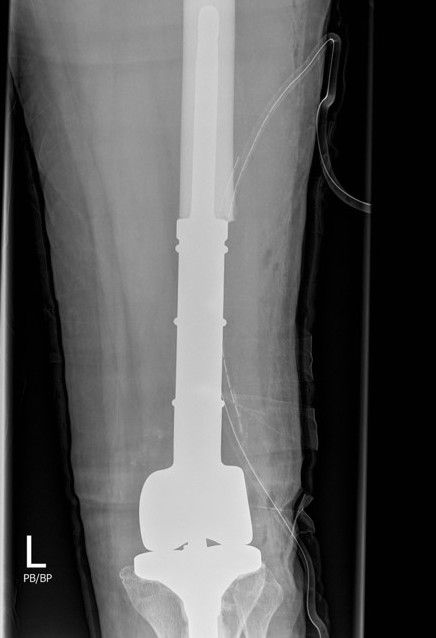

Wide resection and Allograft / Prosthesis Reconstruction

Indications

- extensive soft tissue tumour

- extensive cortical destruction

- impossible joint salvage

- multiple recurrence / failure bone cement